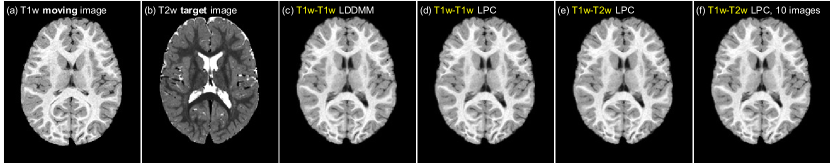

For the multi-modal registration experiment, we use the IBIS 3D Autism Brain image dataset [34]. This dataset contains 375 T1w/T2w brain images from 2 years old subjects. We select 359 of the images for training and use the remaining 16 images for testing. For training, we randomly select T1w-T1w image pairs and perform LDDMM shooting to generate the optimization momenta. We then train the prediction and correction networks to predict the momenta obtained from LDDMM T1w-T1w optimization using the image patches from the corresponding T1w moving image and T2w target image as network inputs. For testing, we perform pair-wise T1w-T2w registrations for all 16 test images, resulting in 250 test cases. For comparison, we also train a T1w-T1w prediction+correction network that performs prediction on the T1w-T1w test cases. This network acts as the “upper-bound” of the potential performance of our multi-modal networks as it addresses the uni-modal registration case and hence operates on image pairs which have very similar appearance. Furthermore, to test prediction performance when using very limited training data, we also train a multi-modal prediction network and a multi-modal prediction+correction network using only 10 of the 365 training images which are randomly chosen for training. In particular, we perform pair-wise T1w-T1w registration on the 10 images, resulting in 90 registration pairs. We then use these 90 registration cases to train the multi-modal prediction networks.

As an example, Fig. 7 shows the result for the LPBA40 dataset. The other three datasets show similar results. Fig. 7(left) shows the histogram of the logarithmically transformed determinant of the Jacobian (log10detJsubscriptlog10det𝐽\text{log}_{10}\text{det}J) for all the methods. A value of 0 on the x-axis indicates no deformation or a volume preserving deformation, >0absent0>0 indicates volumetric shrinkage and <0absent0<0 indicates volumetric expansion. We can see that LPC is closest to LO. LP generates smoother deformations compared with LO, which is sensible as one-step predictions will likely not be highly accurate and, in particular, may result in predicted momenta which are slightly smoother than the ones obtained by numerical optimization. Hence, in effect, the predictions may result in a more strongly spatially regularized deformation. LPP, LPC2 and LPC3 generate more drastic deformations (i.e., more spread out histograms indicating areas of stronger expansions and contractions). Fig. 7(right) shows this effect more clearly; it shows the differences between the histogram of the prediction models and the registration result obtained by numerical optimization (LO). Hence, a method which is similar to LO in distribution will show a curve close to y=0𝑦0y=0.

This assessment also demonstrates that the correction network (of LPC) is different from the prediction network (LP): the correction network is trained specifically to correct minor errors in the predicted momenta of the prediction network with respect to the desired momenta obtained by numerical optimization (LO), while the prediction network is not. Thus, LPC is the only model among the prediction models (apart from LP) that has the explicit goal of predicting the behavior of the LDDMM optimization result (LO). When we use the prediction network in the correction step, the high label overlapping scores are due to more drastic deformations compared with LP, but there is no clear theoretical justification of LPP. In fact, it is more reminiscent of a greedy solution strategy, albeit still results in geodesic paths as the predicted momenta are added in the tangent space of the undeformed moving image. Similar arguments hold for LPC2 and LPC3: using the correction network multiple times (iteratively) in the correction step also results in increasingly drastic deformations, as illustrated by the curves for LPC, LPC2 and LPC3 in Fig. 7. Compared to the label overlapping accuracy boost from LP to LPC, LPC2 and LPC3 do not greatly improve the registration accuracy, and may even generate worse results (e.g., LPC3 on LPBA40). Furthermore, the additional computation cost for more iterations of the correction network + LDDMM shooting makes LPC2 and LPC3 less favorable, in comparison to LPC.

Refer to caption

Figure 7: Distribution of the determinant of Jacobian of the deformations for LPBA40 dataset registrations. Left: histograms of the log-transformed determinant of Jacobian for the deformation maps (log10detJsubscriptlog10det𝐽\text{log}_{10}\text{det}J) for all registration cases. Right: difference of the histograms of log10detJsubscriptlog10det𝐽\text{log}_{10}\text{det}J between prediction models (LP, LPC, LPP, LPC2, LPC3) and LO. For the right figure, the closer a curve is to y=0𝑦0y=0, the more similar the corresponding method is to LO. A value of 0 on the x𝑥x-axis indicates no deformation, or a volume-preserving deformation, >0absent0>0 indicates shrinkage and <0absent0<0 indicates expansion. Best-viewed in color.

3.2.4 Predicting various ranges of deformations